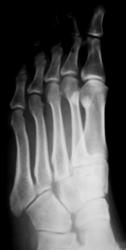

Травма.  Пациент направлен на рентгенографию стопы.

Перелом основания 5 плюсневой без смещения?

Похоже.